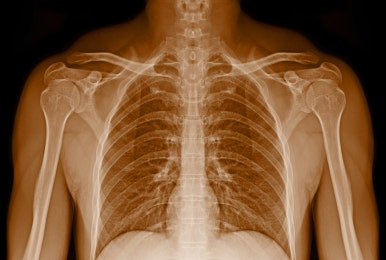

폐암은 폐에 생기는 악성 종양으로, 소세포암과 비소세포암으로 나눌 수 있는데요, 최근에는 비흡연자들 사이에서도 발병률이 점점 높아지고 있습니다.

폐암 사망률은 병기와 치료 시작 시기에 따라 크게 달라질 수 있습니다. 초기에서 발견되면 5년 생존률이 높은 편이지만, 이미 병기가 진행된 상태에서 발견되면 사망률이 급격히 증가한답니다. 예를 들어 1기 폐암은 5년 생존률이 약 50~70% 정도인데, 4기 폐암의 경우 15%로 크게 낮아지죠. 그래서 조기 발견과 치료가 정말 중요해요.